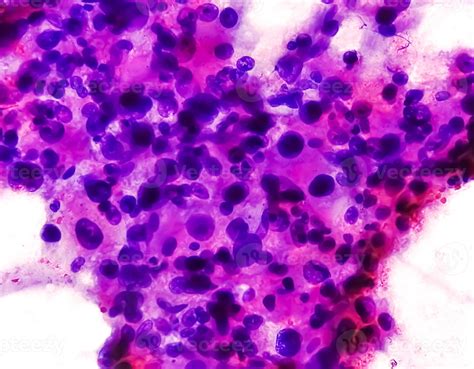

• Biopsy: A sample of the tumor tissue is removed and examined under a microscope to confirm the diagnosis and determine the specific subtype of Spindle Cell Sarcoma.